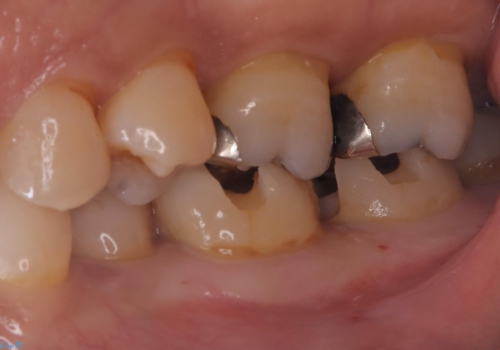

左下7番目の歯の詰め物が外れ、セラミックインレーでのやり替えとなりました。

隣在歯にも保険適用もメタルインレーが入っており、咬合面のインレーと歯質の境目が虫歯になっていたこともあり、合わせてのやり替えとなりました。

左下7番めの歯、フロスを通したらインレーが外れてしまったとのことで、適合具合の精密さや、これを機に白い詰め物にしたいとのことからセラミックインレーでのやり替えとなりました。

また、6番目の歯にも保険適用のメタルインレーが入っており、咬合面インレーと歯質境目にう蝕を認め合わせてのやり替えとなりました。